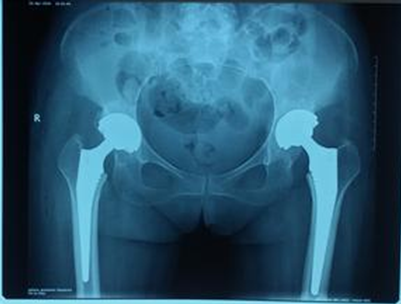

人工全髋关节置换术

人工全髋关节置换是一种应用于髋关节疾病治疗的有效手段,至今已有四十多年的发展历史,已经得到充分的肯定并已经发展成为一种可靠的治疗手段。人工全髋关节置换的目的是缓解疼痛、矫正畸形和重建髋关节功能,从而使那些面临瘫痪或长期卧床的患者,重新站立和行走,回归正常生活轨道。

人工全髋关节由人工髋臼和人工股骨头组成,利用手术方法将人工关节置换被疾病或损伤所破坏的关节面,其目的是切除病灶,清除疼痛,恢复关节的活动与原有的功能。人工关节置换具有关节活动较好,可早期下地活动,减少老年病人长期卧床的并发症等优点。其治疗的适应症如下: